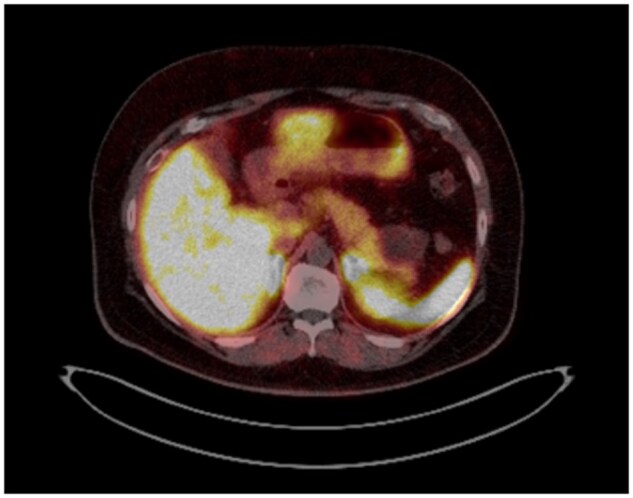

Pancreatic dermoid cyst is an extremely rare benign neoplasm of the pancreas. Pre-operative diagnosis is often difficult due to its rarity and overlapping features with other pancreatic cystic neoplasms. We report a case of a 55-year-old male with an incidental finding of a lobulated complex cystic lesion in the tail of the pancreas on imaging and the challenges to obtain a definitive diagnosis. Due to suspicious features on imaging and elevated CA 19-9 tumour marker, surgical resection was recommended at the Pancreatic Multidisciplinary Team Meeting. The patient subsequently underwent a distal pancreatectomy and splenectomy which confirmed a dermoid cyst.